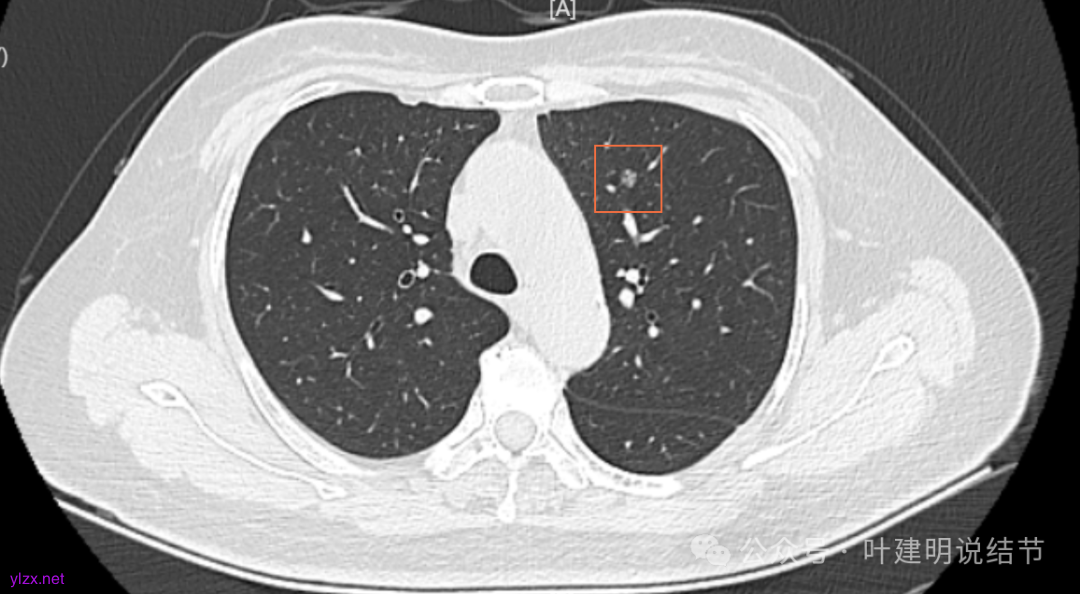

12.2025年4月复查,显示最大结节0.9*0.7。 另外,看几次报告,多发磨玻璃结节数量在上升,从2022年的3个到2025年的7个。

两肺多发磨玻璃结节,主病灶混合密度且有小血管进入,表面不平有毛刺,考虑微浸润性腺癌或浸润性腺癌可能性大,其余部分考虑原位癌或微浸润性腺癌,部分考虑肺泡上皮增生或不典型增生可能。总体上对比2022年说不上太明显的进展。但对于是否手术来讲,我仍倾向当年的意见,左侧的可以考虑近期亚肺叶(个人倾向楔切)切除,右侧的先随访,以后有进展并风险增加再考虑干预处理。因为要拉长两次手术的间隔,这样对机体的创伤与恢复更加有利一些。若定要仍不开刀,则建议要4-6个月复查,不过个人不太主张过于保守随访,对于像主病灶这种有少许实性成分的,不能保证肯定安全。意见供参考!